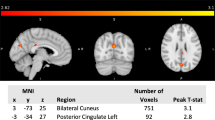

Figure 3; Table 2 show the significant differences in perfusion-based FC between mTBI + PTH and mTBI-PTH patients. mTBI + PTH patients showed changes in perfusion-based FC associated with the insular subregion, mainly in the connectivity with the cingular-opercular network and sensorimotor network. The perfusion-based FC of the insular subregions increased in four clusters in the mTBI + PTH group; specifically, compared with that in the mTBI-PTH group, the perfusion-based FC between the left dAI and the right Rolandic operculum (ROL)/left middle cingulate cortex (MCC) was significantly greater in the mTBI + PTH group, as was the perfusion-based FC between the right vAI and the left MCC and between the left PI and the left supplementary motor area (SMA). Additionally, the perfusion-based FC between the left PI and the right thalamus was significantly lower in the mTBI + PTH group. No significant changes in the perfusion-based FC of the other insular subdivisions (L_vAI, R_PI, R_dAI) were found between two groups.

Group differences in perfusion-based functional connectivity for 3 ROI (R-vAI, L-dAI, L-PI) (Gaussian random field correction, clustering level p < 0.05, voxel level p < 0.001). The cold color indicates decreased CBF and hot color indicates increased CBF in mTBI + PTH patients compared to mTB-PTH patients. L, left; R, right; vAI, ventral anterior insula; dAI, dorsal anterior insula; PI, posterior insula; MCC, middle cingulate cortex; SMA, supplementary motor area; ROL, Rolandic operculum